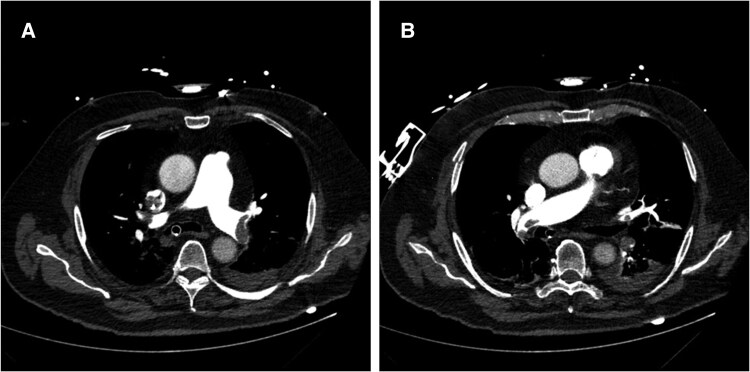

Case summary: A 73-year-old White male was hospitalized in order to perform abdominal surgery. Afterwards, multiple complications led to recurring operations and a prolonged immobilization time. In the aftermath, the patient suffered an in-hospital cardiac arrest and was put on VA-ECMO. A computed tomography pulmonary angiography presented bilateral central PE. Due to contraindications for systemic thrombolysis, successful CDT using a FlowTriever catheter was performed, leading to a reduction of mean pulmonary arterial pressure. ECMO therapy could be terminated in the following days. The patient was eventually discharged without any signs of right heart strain in transthoracic echocardiogram, neurological sequelae or dyspnoea.